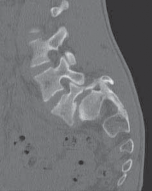

Chapter 63 Hemivertebra Excision Daniel J. Hedequist and John B. Emans DEFINITION A hemivertebra is a congeni…